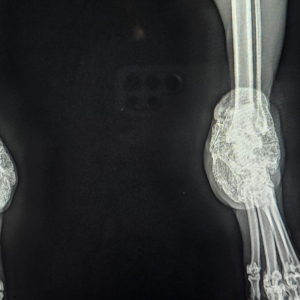

Scottish Fold

Der Gendefekt betrifft den gesamten Knorpelapparat.

Folgen:

- chronische Gelenkschmerzen

- Versteifungen

- Lahmheit

- eingeschränkte Beweglichkeit

Viele Katzen zeigen Schmerzen erst spät – wenn sie nicht mehr springen oder sich zurückziehen.